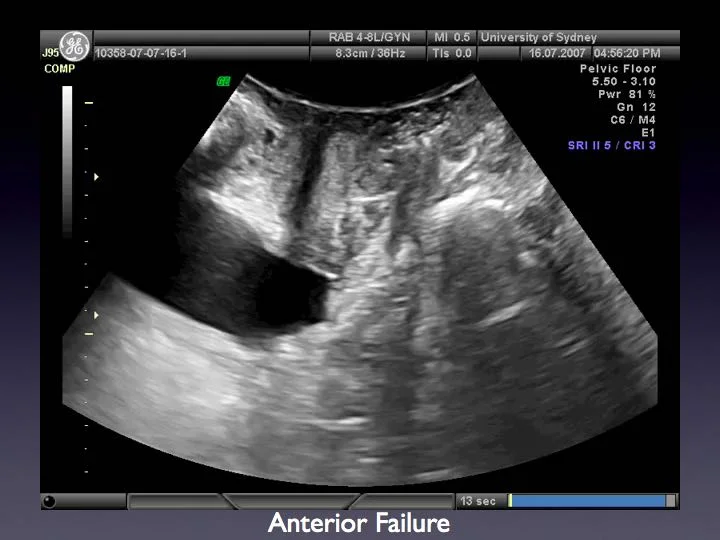

Sydney pelvic floor health. Sydney pelvic floor health. Given that these pelvic symptoms persist or continue to progress it is important to consult your gp or pelvic physiotherapist to formulate an individualised management program to optimise your long term pelvic health and quality of life. Ethics committee approval number. Research and clinical services in urogynaecology and pelvic floor medicine since 2005.